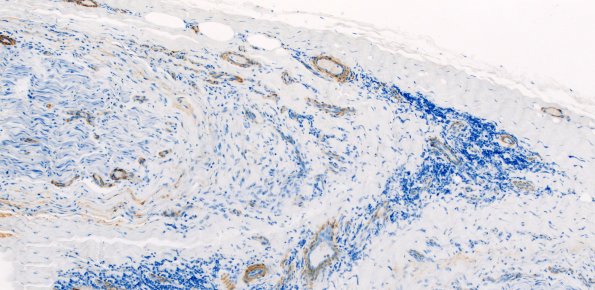

5C3 Perineuritis (Case 5) SMA 10X

This SMA immunostain fails to show damage to most vessel walls. (SMA IHC)